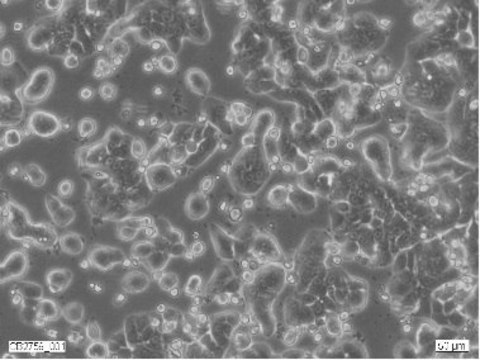

HT29 Cell Line human

Morphology:

Epithelial

Human Caucasian colon adenocarcinoma

Isolated from a primary tumour in a 44 year old Caucasian female. Forms a well-differentiated adenocarcinoma consistent with colony primary, grade I. Tumours also form in steroid treated hamsters. Has the following HLA profile A1,3; B12,17; Cw5.